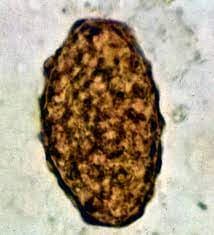

تخم غیربارور متشکل از یک توده گلوبولار نامرتب و معمولا باریک‌تر و کشیده‌تر از تخم بارور است در اثر مواد صفراوی داخل روده به رنگ قهوه‌ای در می‌آیند.

Range 85-95*35-45 µm (average: 90*40 µm)